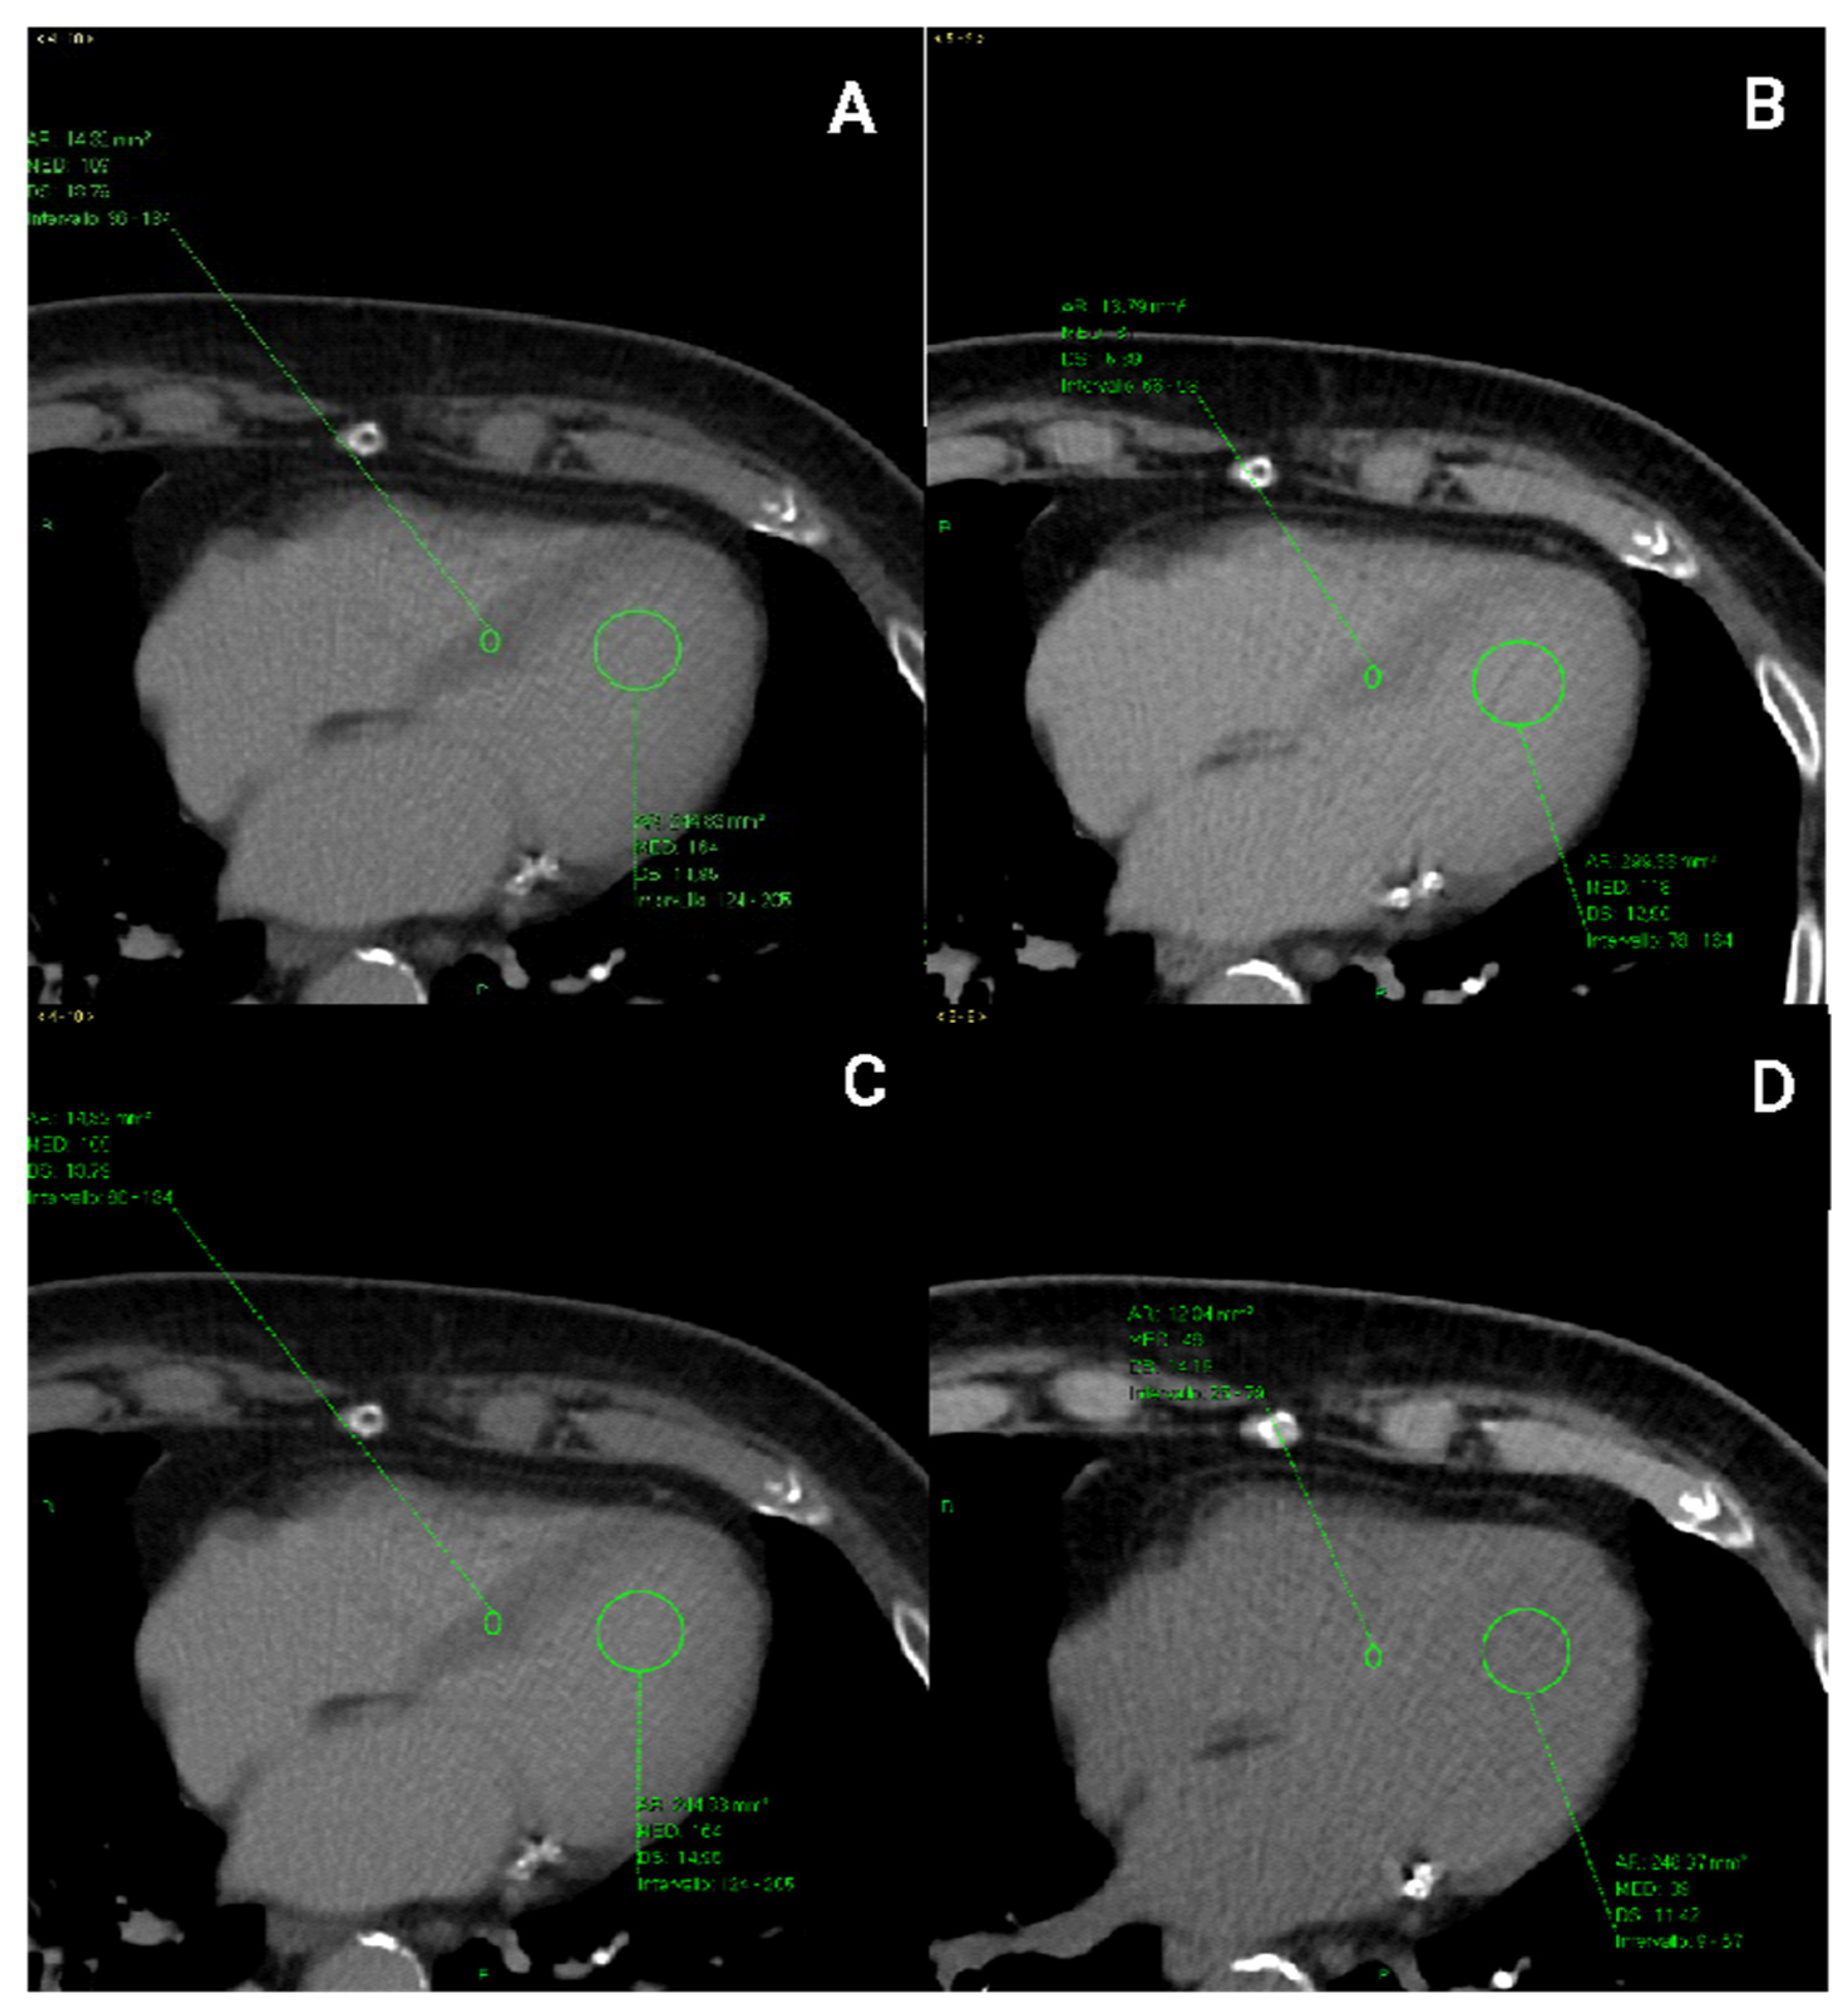

2.4. CT Image Analysis